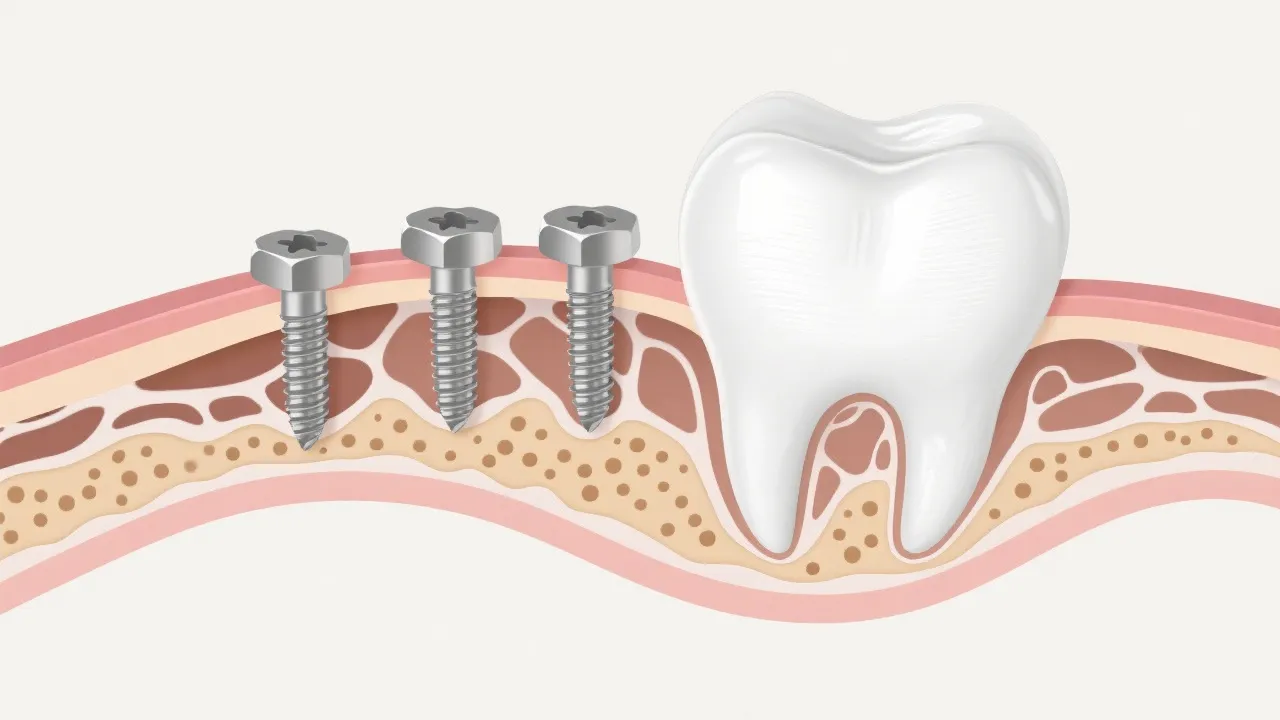

Dental implants rely on a process known as osseointegration, where the implant material, typically titanium, fuses directly with the jawbone. This process requires adequate bone health and density, which can be compromised in individuals with osteopenia. The effectiveness of osseointegration can be drastically affected by the quality and thickness of the jawbone, which is essential for distributing bite forces evenly. Advanced imaging techniques, like cone-beam computed tomography (CBCT), allow for a detailed assessment of bone quality and help determine the most suitable approach for implant placement. However, advancements in dental technology and techniques offer potential solutions for patients affected by this condition.

For individuals with osteopenia, the primary concern in implantology is the reduced bone mineral density, which can affect the implant's anchorage in the bone. A soft and thin jawbone can lead to complications, including implant migration or even failure, if osteopenia is not adequately addressed during the planning phase. Thus, it becomes imperative for dental professionals to conduct a thorough evaluation of the patient's bone density prior to any surgical interventions. This evaluation typically involves tools like dual-energy X-ray absorptiometry (DEXA) scans, which measure bone mineral density and help in formulating personalized treatment plans.

Advances in dental implantology include the use of mini dental implants and modified techniques capable of addressing bone density issues. These mini implants, which require less bone density compared to traditional implants, can reduce the invasiveness of the procedure while still providing adequate support for dental restorations. Furthermore, patients with osteopenia may benefit from specialized implant designs, such as those with improved surface structures to enhance osseointegration, increasing the surface area for better integration with the bone.

Adjunctive bone augmentation procedures have also emerged as effective techniques to prepare the jaw for implant placement. These procedures can involve bone grafting, sinus lifts, or ridge expansion, all of which aim to create a more stable foundation for implant placement. These surgical interventions encourage the body to generate new bone and improve the overall density, giving patients a higher success rate for their dental implants. Moreover, the use of growth factors, like platelet-rich plasma (PRP), has gained traction as a method to accelerate the healing process and enhance bone regeneration.